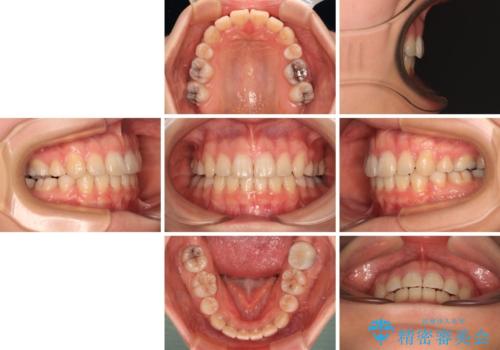

- 口元の突出感を気にして来院された患者様です。

口元を積極的に引っ込めるために、上下左右の第一小臼歯を4本抜歯することとし、ワイヤー装置による矯正治療を行うこととしました。

上下前歯がくちばしのように突出していましたが、抜歯矯正により口元が引っ込み、唇が閉じやすくなり、鼻の下の膨れた感じも解消されました。